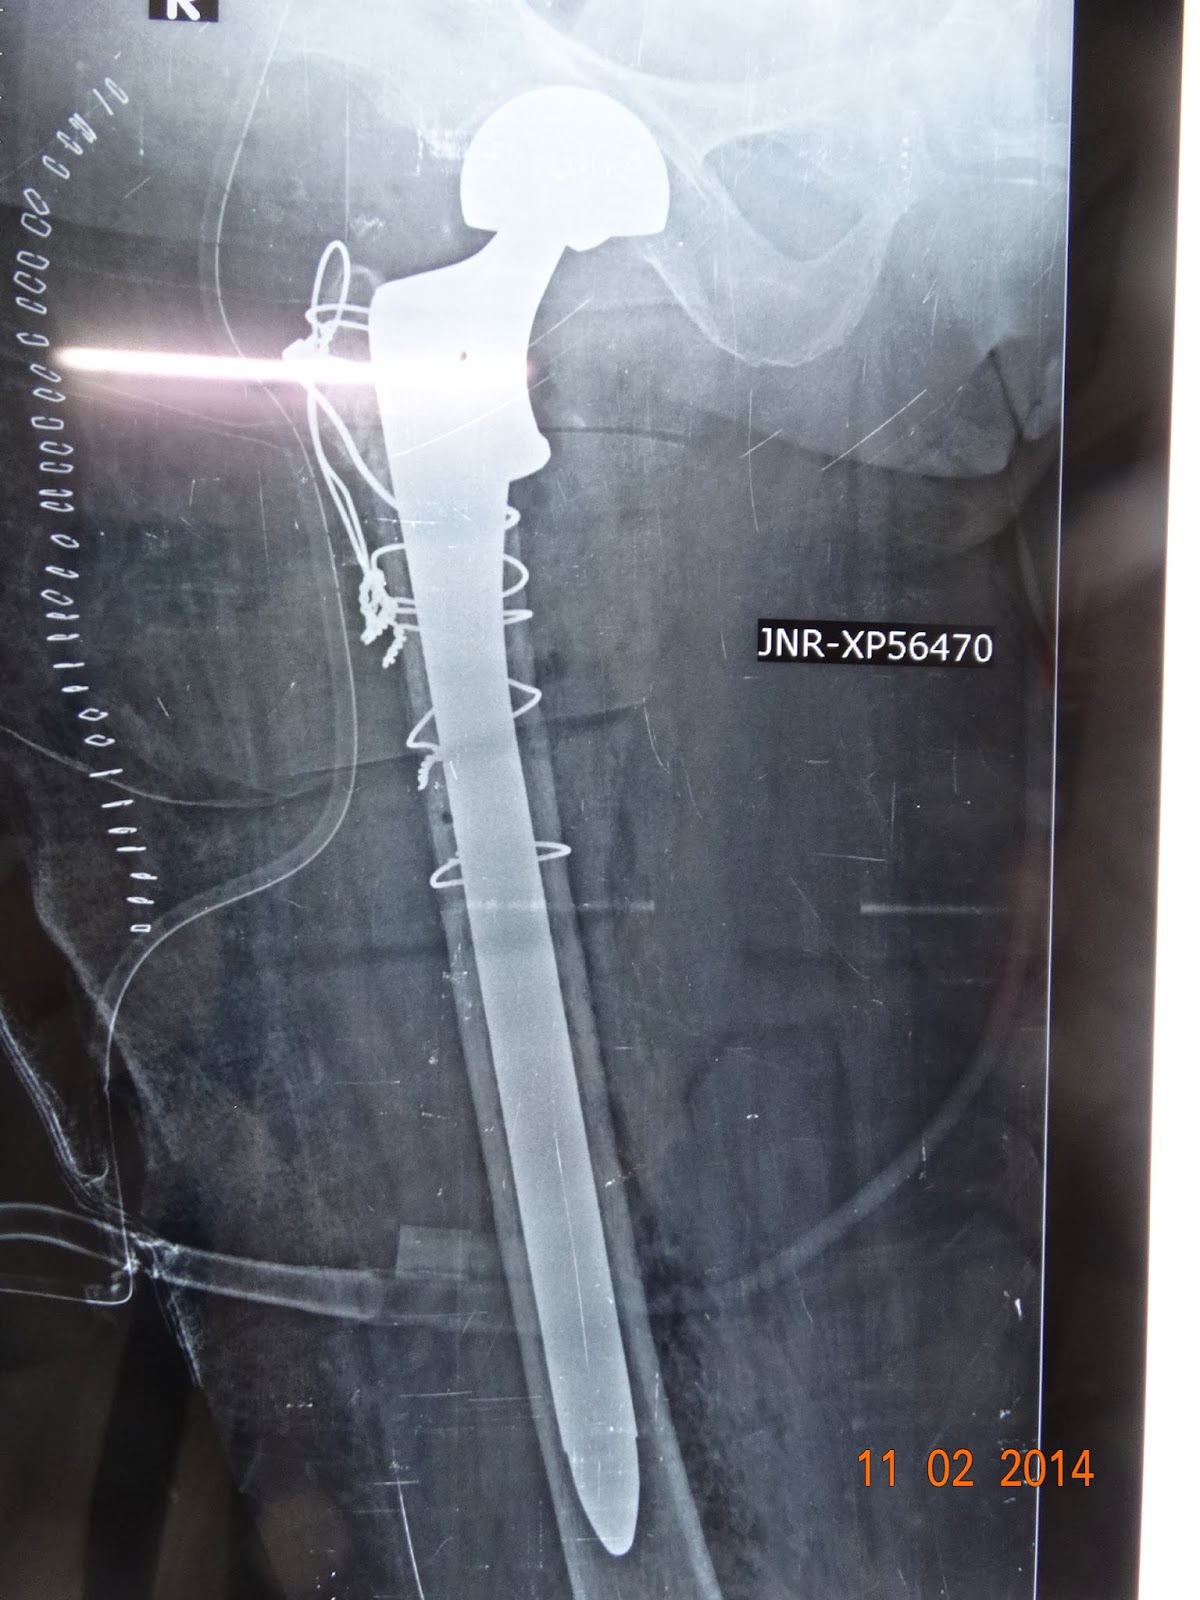

COMPLEX REVISION HIP SURGERY IN A 73 YR OLD WITH FAILED HIP SURGERY (done elsewhere) ,Bangalore , INDIA

73 YR old female , operated elsewhere with a failed hip fracture surgery came to us , with this

we planned a revision -calcar replacement stem(intraop gram stain negative for bacteria)

cables and wiring (charnleys ) for trochanter

wiring of trochanter

calcar replacement long stem- in place with wires

bipolar head introduced

prosthesis reduced

wiring of trochanter done with cable(CHARNLEY)

post op x ray